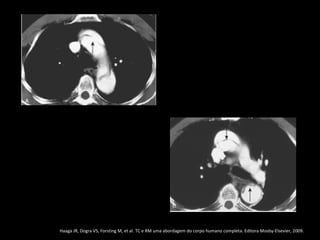

Dissecção aórtica

Angiotomografia

Diagnóstico: identificação do flap intimal, que se

apresenta como uma fina membrana separando a

luz falsa da verdadeira;

Sensibilidade e especifidade acima de 95% na

detecção do flap intimal;

Após diagnóstico: localizar, definir envolvimento de

ramos aórticos e identificar fatores agravantes

relacionados à própria aorta.